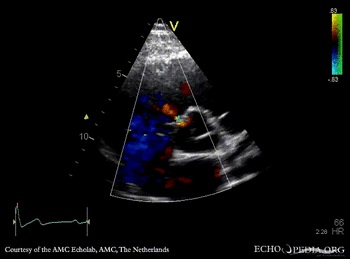

A5CH with Color Doppler